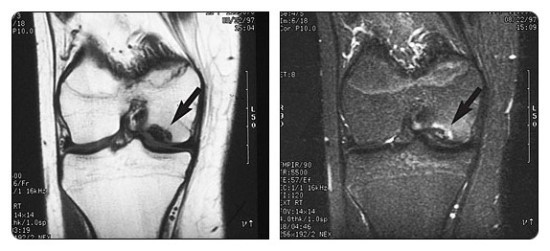

원반형 반월판(Discoid meniscus)이 인구의 3% 정도로 발생하는 흔한 변이에 해당하는데, 반월판의 형태학적인 거대화로 나타난다. (그림 46-7) 환자는 대개 무릎을 신전하고 굴곡할 때 염발음을 나타낸다. 이는 관상면 상에서 최적으로 진단되고 시상면 상에서는 그렇지 않은데, 기술상의 다양함이 나타날 수 있다. 대퇴외과의 중간 레벨을 관통한 관상면 MRI 영상에서 대퇴외과의 중간 포인트 아래로 가운데 부위로 이어지는 반월판이 원반형 반월판(discoid meniscus)으로 불린다.

△ 그림 46-7. 외측 원반형 반월판

중간 대퇴외과 레벨을 통과하는 관상면 T1 강조 시퀀스는 외측 원반형 반월판으로 나타나는 외측 반월판이 외측 대퇴외과의 중간 포인트 아래 가운데 부위로 연장됨을 보여준다. (화살표) 정상적인 내측 반월판은 내측 대퇴내과로 이어짐은 보이지 않는다. M = 내측, L = 외측

△ 원반형 반월판 (Discoid meniscus) - 관상면 양성자 밀도 강조 MRI

(이미지 출처 : http://en.wikipedia.org/wiki/Discoid_meniscus)